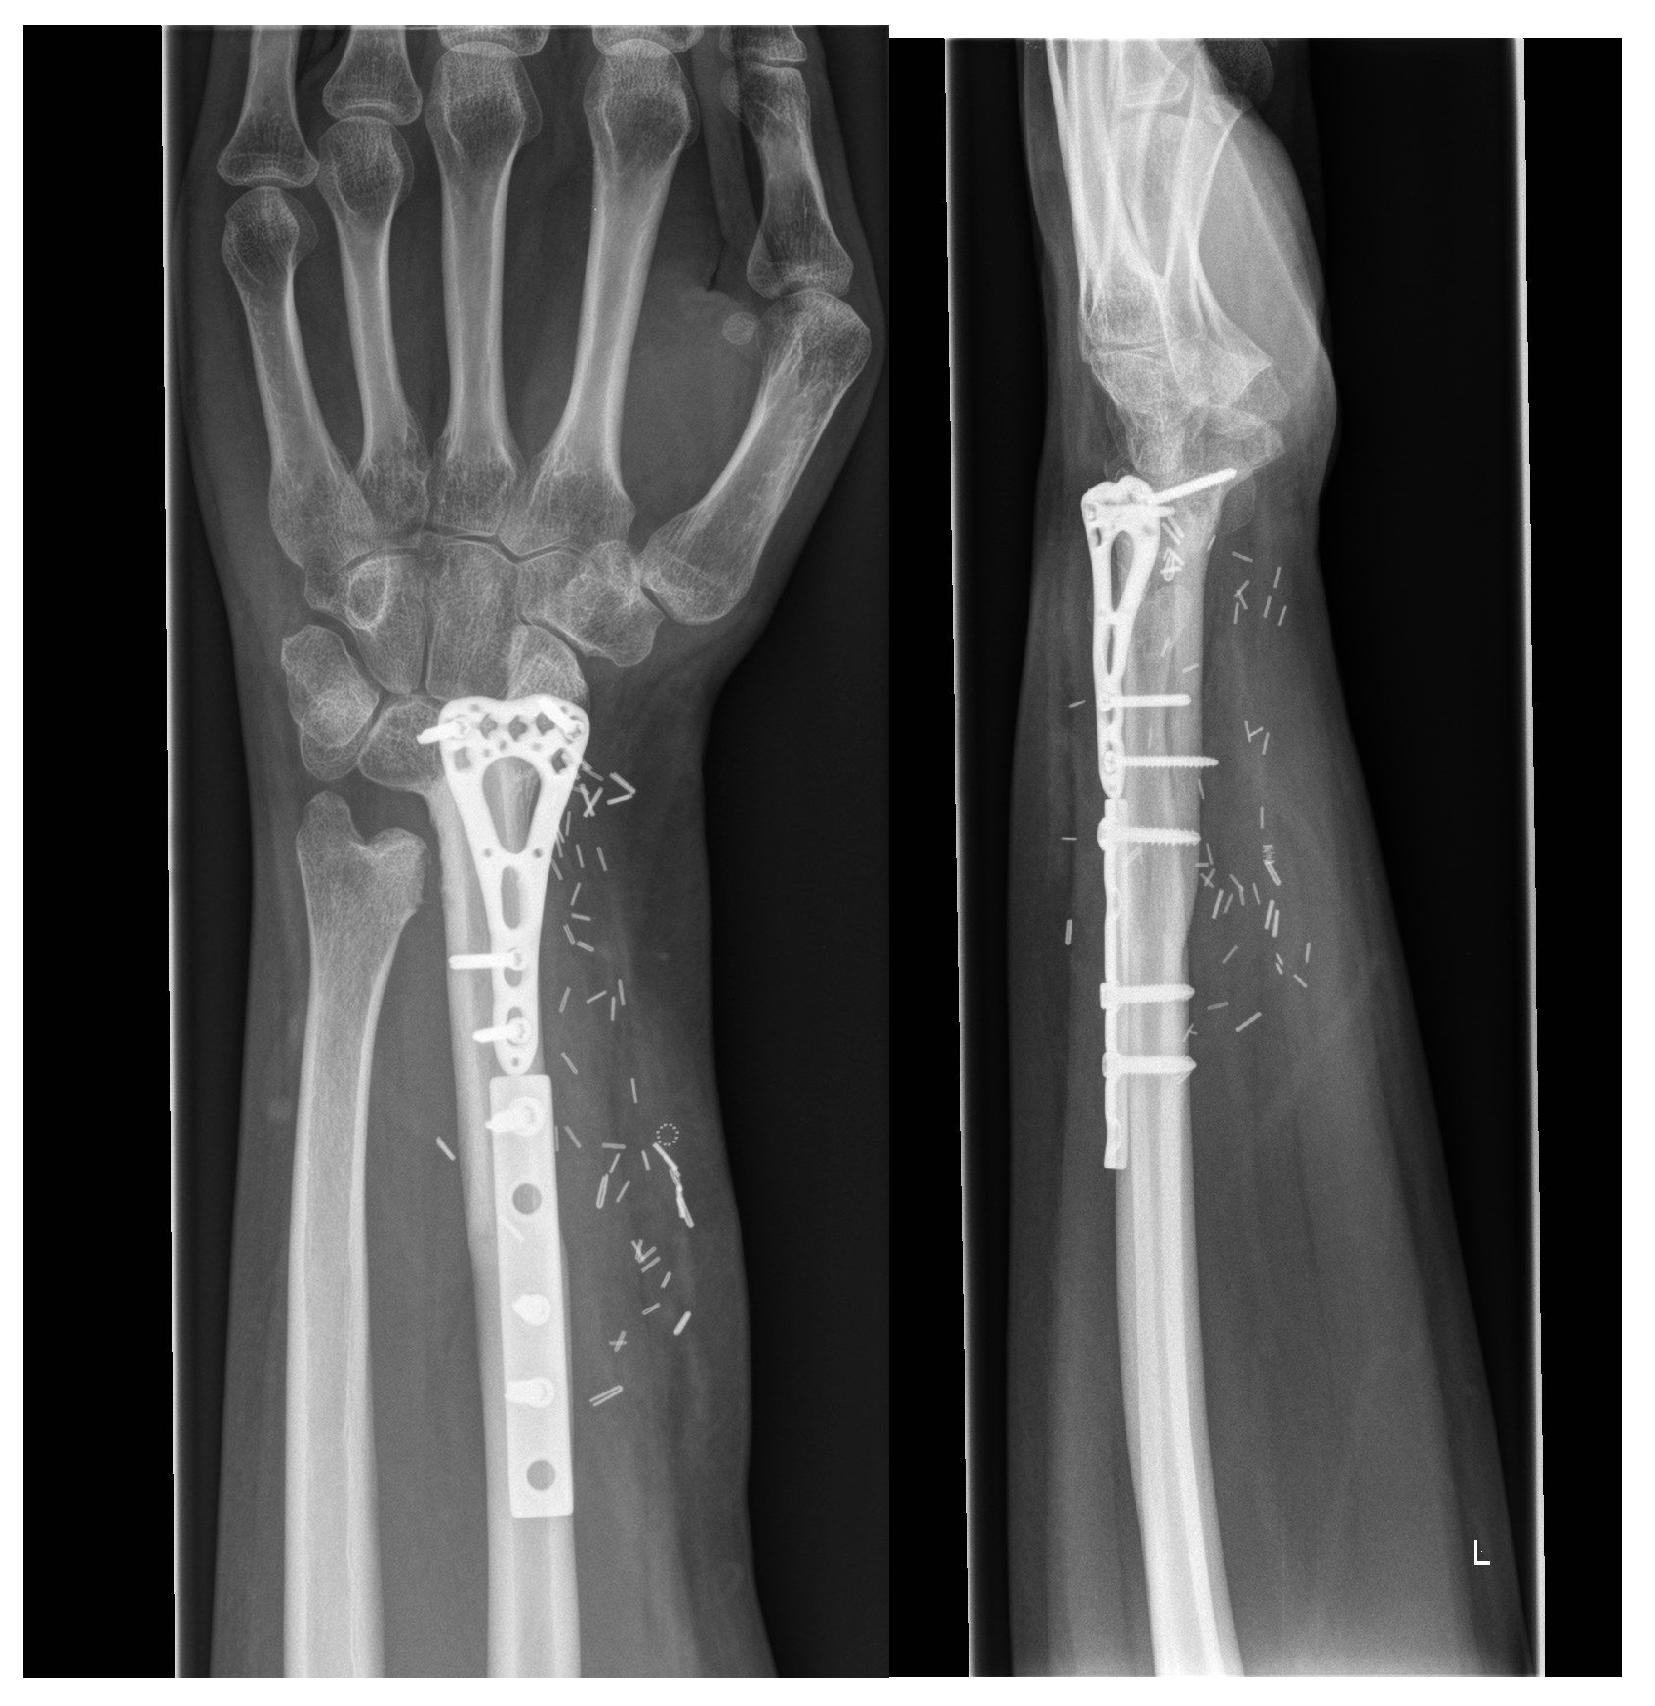

3.2.2. Arthrodesis of the Distal Radius and Middle Hand Using a Triangular-Shaped Vascularized Osteocutaneous Fibula Flap

| Case 3 | Complete wrist, distal radius and proximal metacarpals | Benign, aggressive bone tumor | 53 | 41 | 8 cm | Vascularized osteocutaneous triangular fibula | Wrist arthrodesis | N/A N/A | 0-0-0° 80-0-40° | 70% | MMWS = 45 DASH = 30 | yes | |